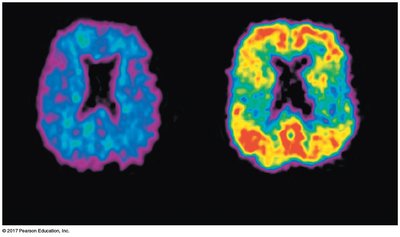

Radioactive Isotopes